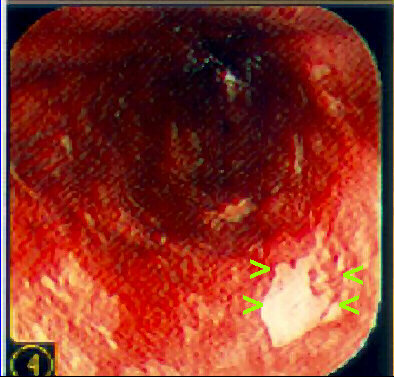

Ballon cytology: many "low grade" dysplastic squamous cells were seen. Increased N/C ratio, some binucleated cells, moderate nuclear hyperchromasia in other cells. At endoscopy, confirmation of the diagnosis, and identification of the dysplastic areas by negative lugol staining ( See article by Freitag et al. Dis Esophagus 1999;12:191-195.). Biopsy showed low grade intraepithelial squamous lesion. In Taquara, RS, Brazil, there is a high incidence of squamous cell carcinoma of the esophagus, and we are conducting a population surveillance with a special ballon for cell collection. This is one of the patients with dysplasia that were detected and treated (mucosectomy).